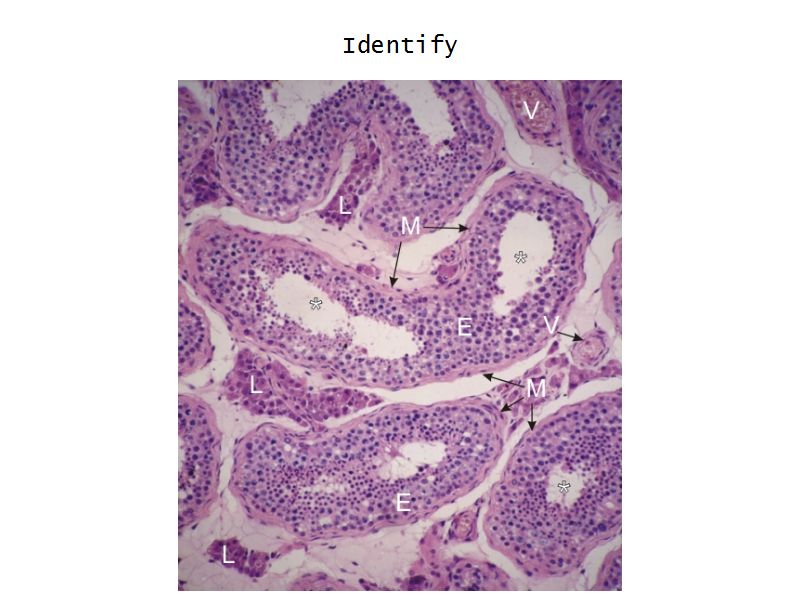

Testis

Slide 84

Testis

- Tunica albuginea

- Lobuli

- Seminiferous tubuli

- Epididymus

- Ductus deferens

Tunica albuginea

- Thick fibrous CT capsule

- Forms septae

- Divide testis into lobuli

Lobuli

- Pyramidal shaped compartments

- Contain 1 - 4 seminiferous tubules each within

- Meshwork of loose CT

- AVN

- Leydig cells

Leydig cells

- Interstitial cells

- Surrounded by rich AVL

- Large round - polygonal shape with clear cytoplasm

- Large central nucleus

- Endocrine - testosterone

Seminiferous tubuli

- Site of spermatozoa production

- 150 - 250 µm diameter

- Complex stratified epithelium

- Blood-testis barrier

Seminiferous epithelium

- Two types of cells

- Spermatogenic cells

- Sertoli cells

- 4 - 8 cell layers thick

- Forms the blood-testis barrier

Sertoli cells

- Complex columnar shape

- Basal lamina to lumen

- Irregular outline

- Envelope developing germ cells

- Large pale nucleus with indentations & large nucleolus

- Occludens junctions with adjacent cells

- Establish blood-testis barrier